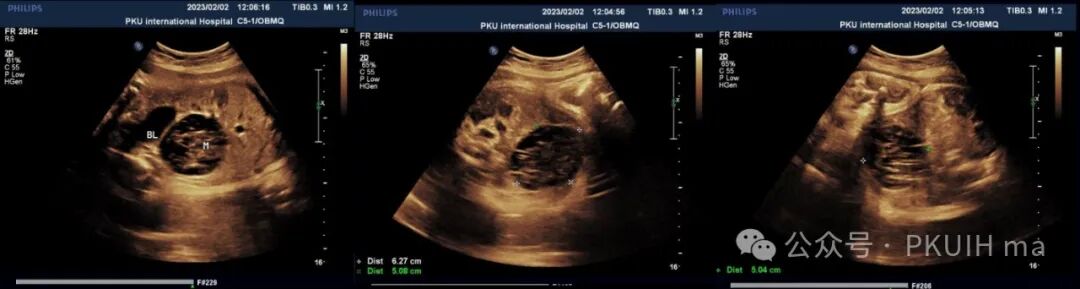

上图是一例孕36周+突然发现胎儿右下腹膀胱后方见一复杂囊性肿物,大小约6.3x5.0x5.1cm,边界清,形态规则,内回声不均匀,似囊实性改变。(该胎儿为女性胎儿)

CDFI观察肿物内部未见明显血流信号